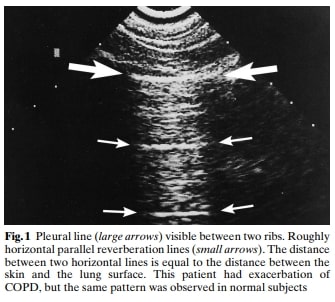

A significant portion of our current knowledge in lung ultrasound stems from Dr. Daniel Lichtenstein’s landmark paper in 1998. The paper discussed the use of artifacts to differentiate between pulmonary edema and COPD. Since that time some of the nomenclature was later redefined by Dr. Lichtenstein and what was then described as “roughly horizontal parallel reverberating lines” is now called A-lines and what was then called comet-tail artifact is now referred to as B-lines (defined as stretching below 16cm of depth). Additionally comet-tails artifact is now referred to as Z-lines and are defined distinct from B-lines and have no clinical significance:

“A” or A-lines can be regarded as a normal lung artifact, but can also be seen in pneumothorax, asthma exacerbation, and COPD exacerbations in the right clinical context.